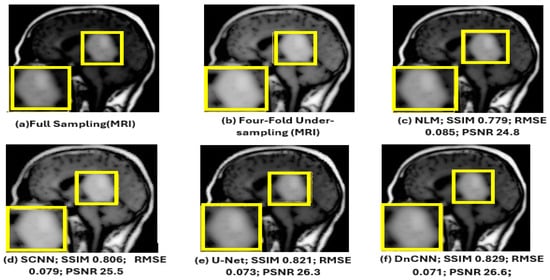

| NLM [4] | 0.779 ± 0.036 | 0.085 ± 0.007 | 24.8 ± 0.7 |

| SCNN [14] | 0.806 ± 0.034 | 0.079 ± 0.007 | 25.5 ± 0.7 |

| U-Net [11] | 0.821 ± 0.032 | 0.073 ± 0.006 | 26.3 ± 0.6 |

| DnCNN [13] | 0.829 ± 0.031 | 0.071 ± 0.006 | 26.6 ± 0.6 |

| DenseNet | 0.833 ± 0.030 | 0.070 ± 0.006 | 26.8 ± 0.6 |

| CA-AGF | 0.839 ± 0.031 | 0.072 ± 0.006 | 26.5 ± 0.6 |

| DWT | 0.819 ± 0.032 | 0.074 ± 0.006 | 26.2 ± 0.6 |

| ACNCL-U-Net | 0.889 ± 0.026 | 0.060 ± 0.005 | 27.9 ± 0.5 |

| ACNCL-DnCNN | 0.893 ± 0.025 | 0.059 ± 0.005 | 28.1 ± 0.5 |

| ACNCL-DenseNet | 0.881 ± 0.027 | 0.063 ± 0.005 | 27.6 ± 0.5 |

| ACNCL-CA-AGF | 0.890 ± 0.028 | 0.060 ± 0.005 | 28.3 ± 0.5 |

| ACNCL-DWT | 0.868 ± 0.029 | 0.066 ± 0.006 | 27.0 ± 0.5 |